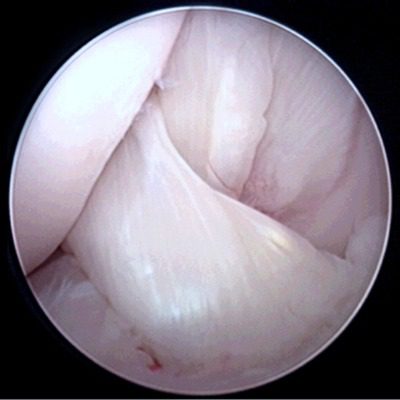

Normal Cranial Cruciate Ligament